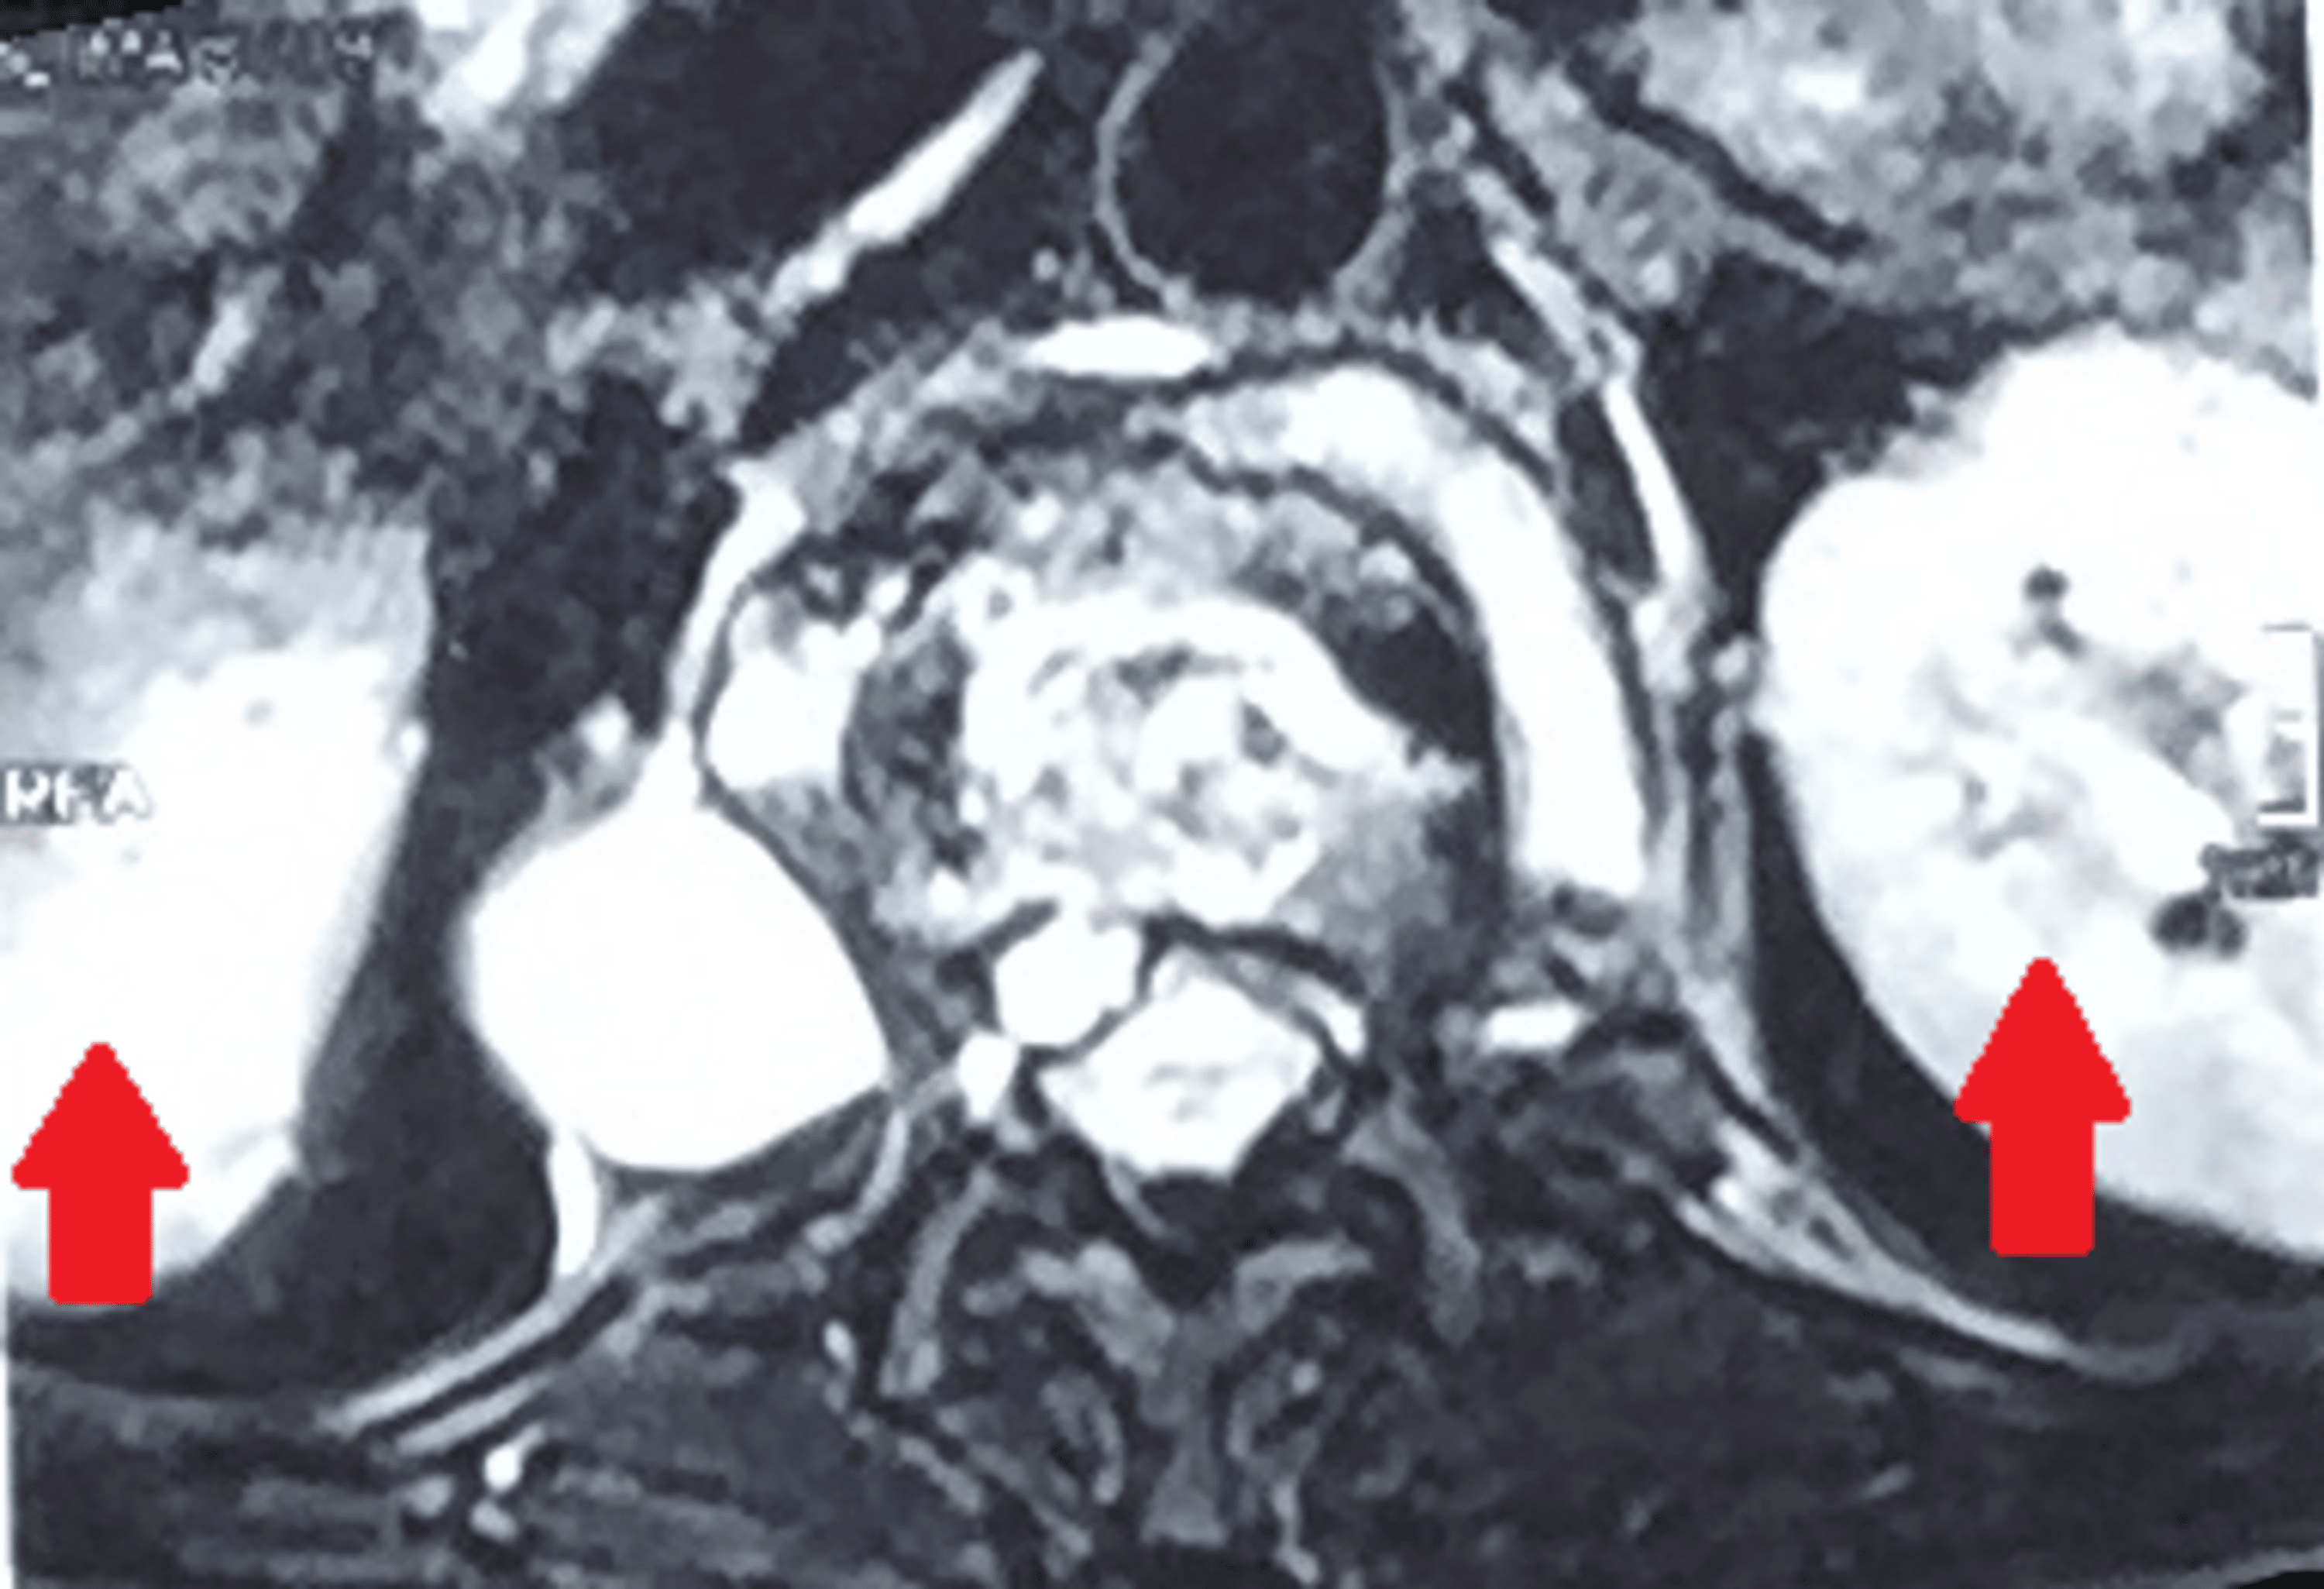

38yo male with multidrug resistant tuberculosis. The largest abscess I Multidrug-Resistant Spinal Tuberculosis Spinal tuberculosis (tb) is the most common extrapulmonary form of tuberculosis. In both developing and developed countries, tb has been on the rising trend due to factors such as increasing hiv coinfection, multidrug resistance of the organism, and global migration. It is multiresistant (mdr) if both isoniazid and rifampicin are not effective, and. Multidrug-Resistant Spinal Tuberculosis.

MultidrugResistant Tuberculosis of the Spine With Bilateral Psoas and Multidrug-Resistant Spinal Tuberculosis In both developing and developed countries, tb has been on the rising trend due to factors such as increasing hiv coinfection, multidrug resistance of the organism, and global migration. It is multiresistant (mdr) if both isoniazid and rifampicin are not effective, and. Spinal tuberculosis (tb) is the most common extrapulmonary form of tuberculosis. Multidrug-Resistant Spinal Tuberculosis.

Cureus MultidrugResistant Tuberculosis of the Spine With Bilateral Multidrug-Resistant Spinal Tuberculosis In both developing and developed countries, tb has been on the rising trend due to factors such as increasing hiv coinfection, multidrug resistance of the organism, and global migration. Spinal tuberculosis (tb) is the most common extrapulmonary form of tuberculosis. It is multiresistant (mdr) if both isoniazid and rifampicin are not effective, and. Multidrug-Resistant Spinal Tuberculosis.

Cureus MultidrugResistant Tuberculosis of the Spine With Bilateral Multidrug-Resistant Spinal Tuberculosis In both developing and developed countries, tb has been on the rising trend due to factors such as increasing hiv coinfection, multidrug resistance of the organism, and global migration. It is multiresistant (mdr) if both isoniazid and rifampicin are not effective, and. Spinal tuberculosis (tb) is the most common extrapulmonary form of tuberculosis. Multidrug-Resistant Spinal Tuberculosis.